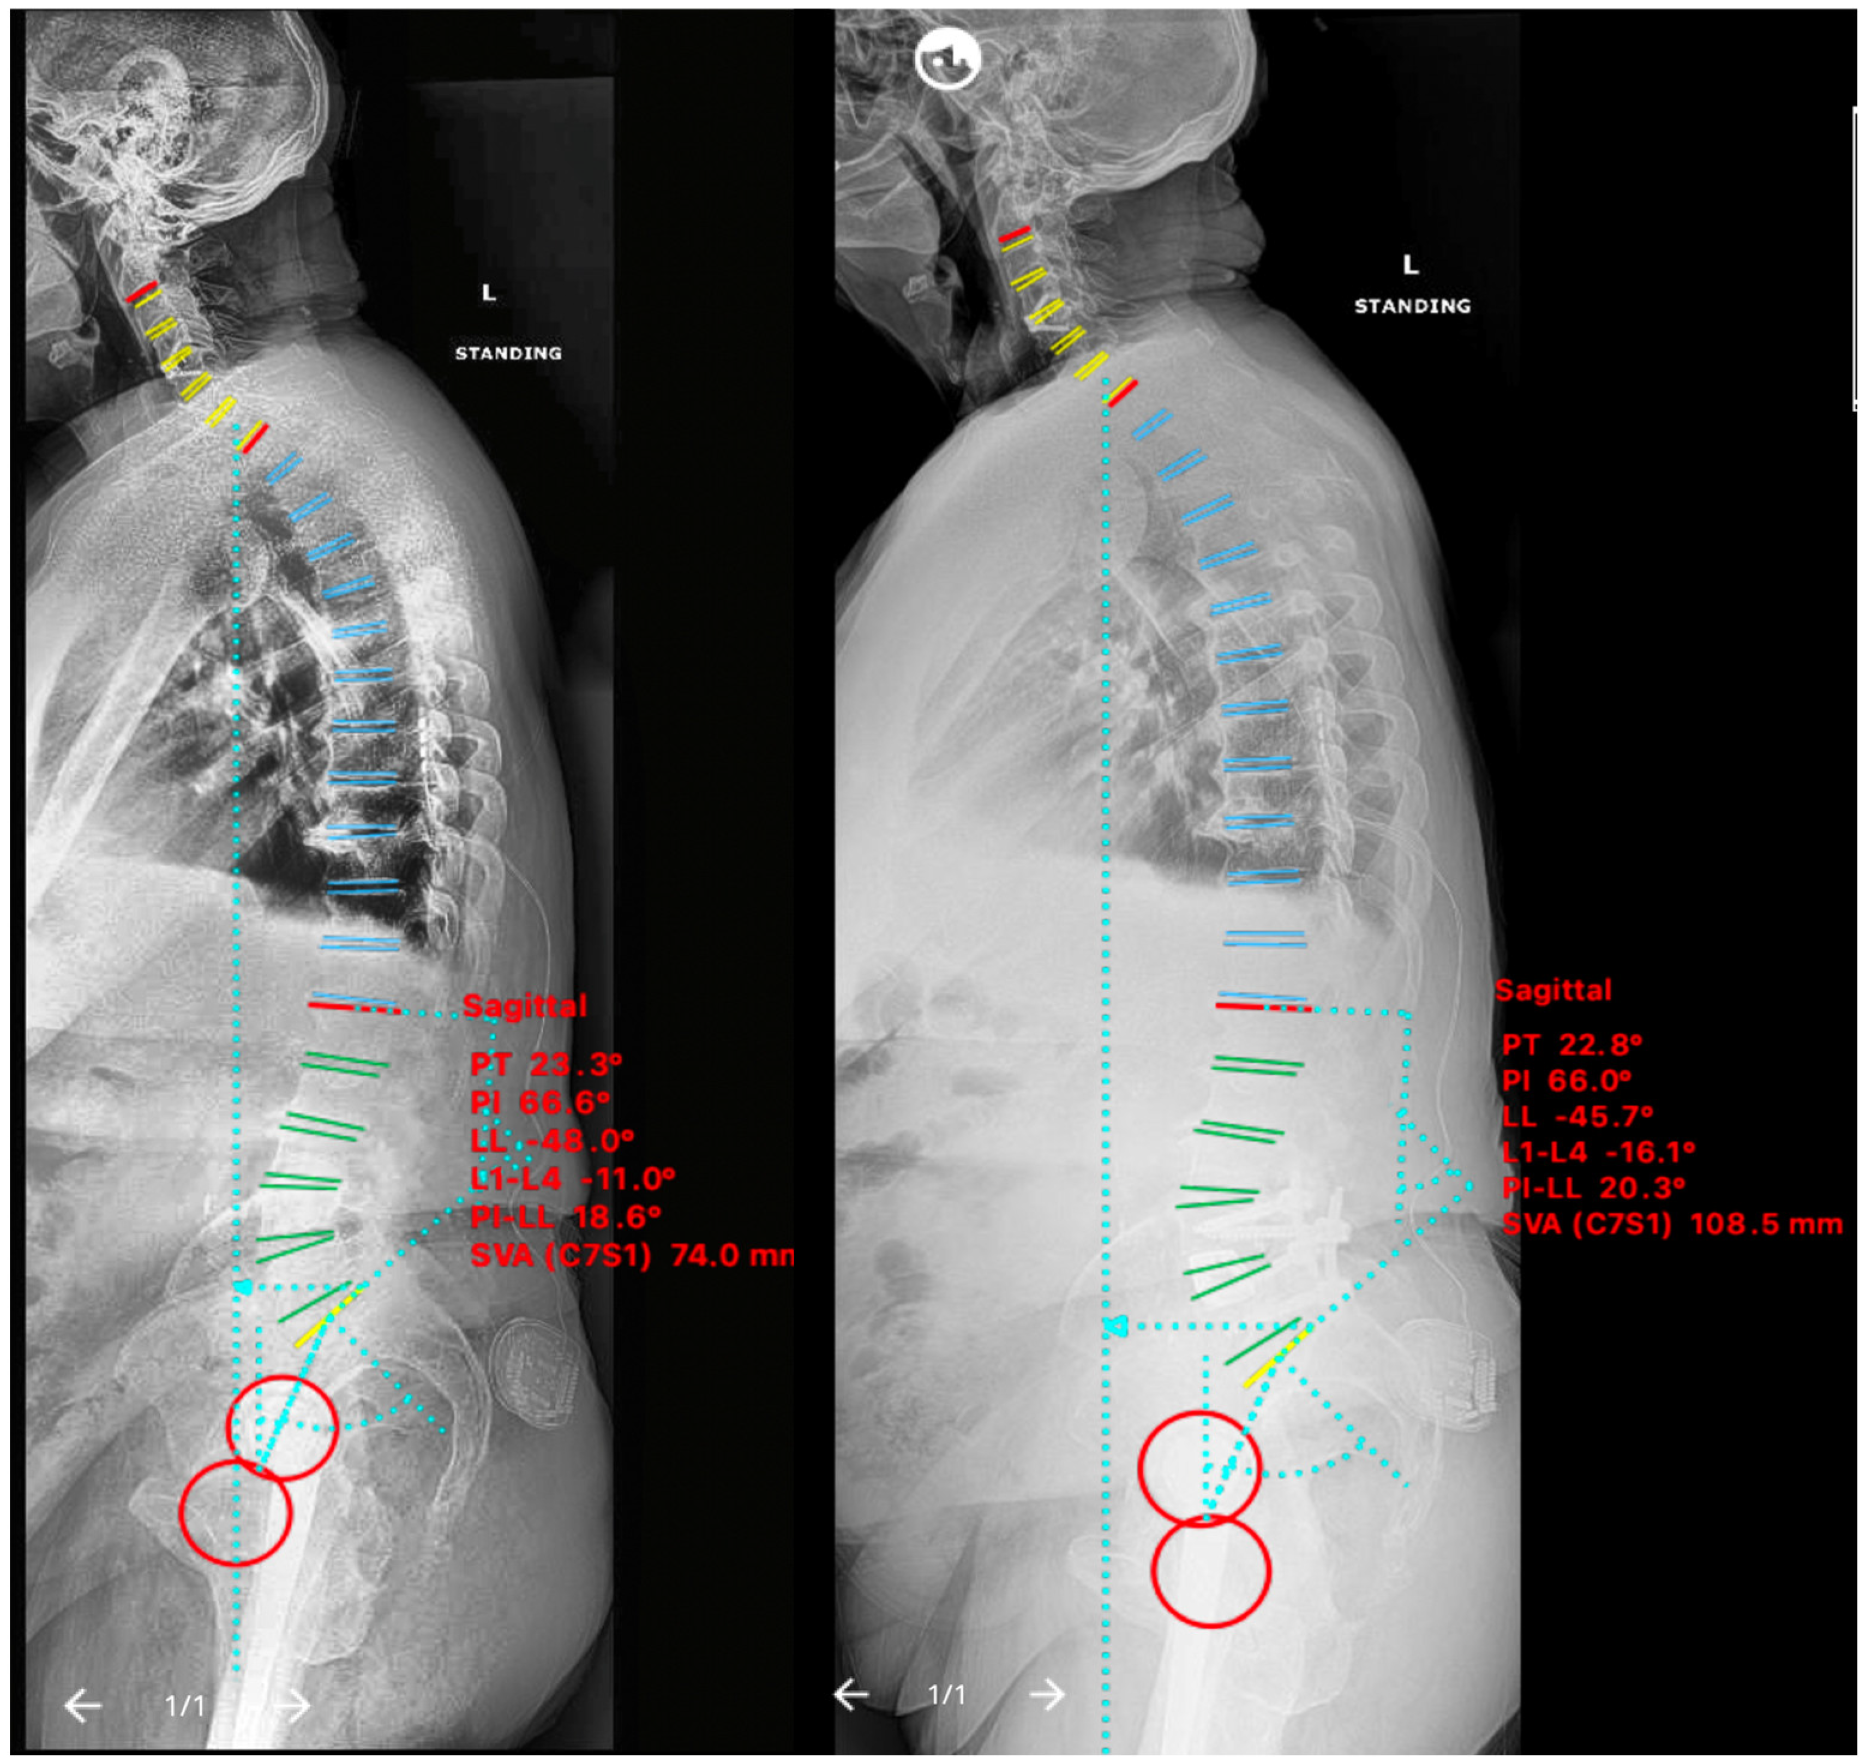

2.5. Non-ACR Cases

2.5.1. Case IV

2.5.2. Case V